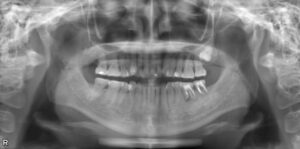

下顎4本欠損症例

BEFORE AFTER 51歳女性/下顎4本欠損/インプラント埋込手術 【治療内容】 右下前歯と左下臼歯の動揺と痛みが…